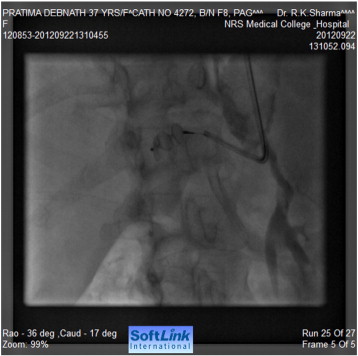

Tran-femoral catheter passage beyond the bifurcation of the abdominal aorta was not possible due to total occlusion and trans-radial aortic angiography showed a long segment of total occlusion (coarctation of abdominal aorta) just below the origin of both renal arteries, multiple dilated collaterals connecting both upper and lower aortic segments with a huge aneurysm involving gastroduodenal artery (Fig. 2, Fig. 3 ;  Fig. 4). Lower thoracic aorta was calcified and arch vessels origins and proximal aorta were normal. The blood pressure within the aneurysm was 190/110 mmHg (Fig. 5).

Selective angiography of feeding vessel to aneurysm via a right Judlins ...

Selective angiography of feeding vessel to aneurysm via a right Judlins catheter.